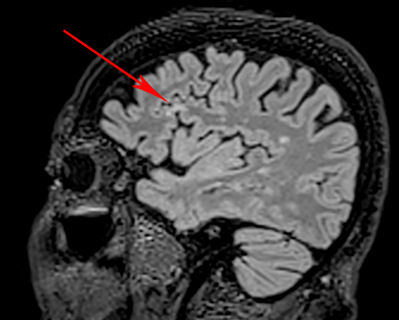

Indicate the type of lesion